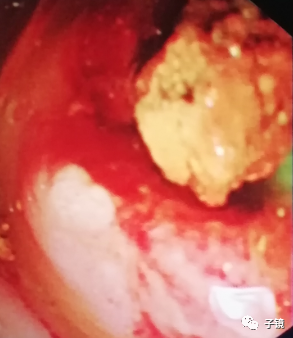

加力往下拖,看到数个不完整的黄色碎石出来了,应该是结石给予取石球囊压碎了。

取石球囊怎么取石“ERCP球囊取石细节讨论”学习笔记_https://www.jmylbn.com_新闻资讯_第8张